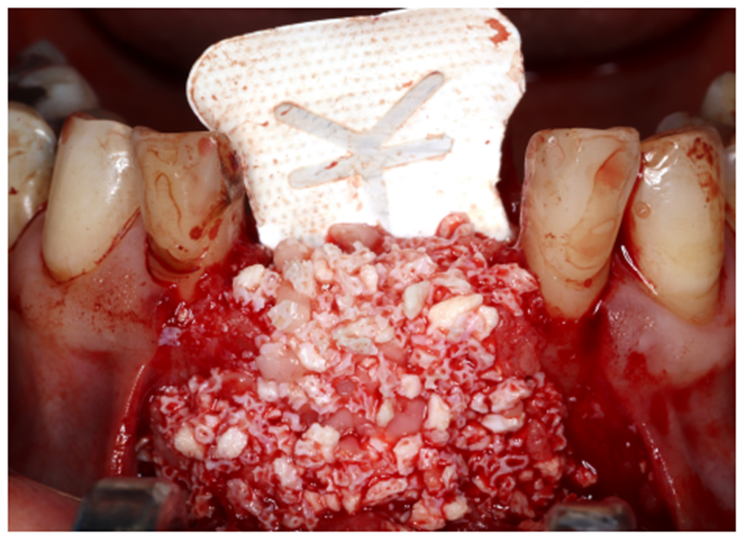

Paciente RV, do sexo masculino de 52 anos, compareceu a nossa clínica com queixa estética e funcional dos dentes incisivos centrais superiores. No exame clínico observou-se doença periodontal severa com presença de bolsa periodontal e perda óssea marginal maior do que 7 mm (Figura 1). Foi realizado em nossa escola (Beo – Ensino Odontológico Avançado) uma tomografia computadorizada para melhor planejamento cirúrgico do caso, onde confirmamos a necessidade de regeneração óssea guiada com membrana Cytoplast com reforço de titânio, devido à perda óssea vertical maior do que 7 mm (Figura 2). Após definição do planejamento cirúrgico, foi realizado a exodontia dos incisivos centrais superiores, limpeza cirúrgica da região e osteotomia periférica para melhor preparo do leito receptor do material de enxertia de lenta reabsorção Bio-Oss (Geistlich) e da membrana Cytoplast com reforço de titânio 30 mm X 40 mm (Figuras 3,4 e 5). Após estabilização da membrana, foi realizado a sutura com fio do tipo Cytoplast 3.0 mm devido a sua alta plasticidade, diminuindo o risco de deiscência de sutura (Figura 6).